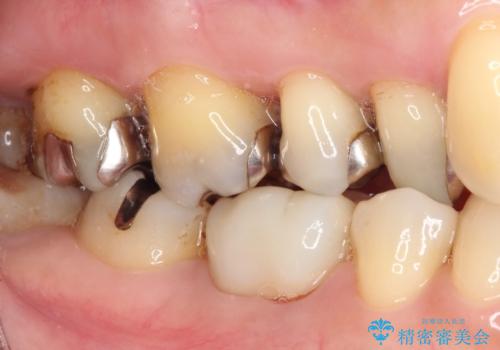

- 奥歯の銀歯をセラミックの白い歯にして、しみる症状も改善したいとのことで来院された患者様です。

知覚過敏の症状が強い歯と、銀歯の範囲や銀歯の下のむし歯が大きい歯は、インレー修復では対応が難しいためオールセラミッククラウンで、インレー修復で対応が可能な歯ではセラミックインレーにて修復することとしました。